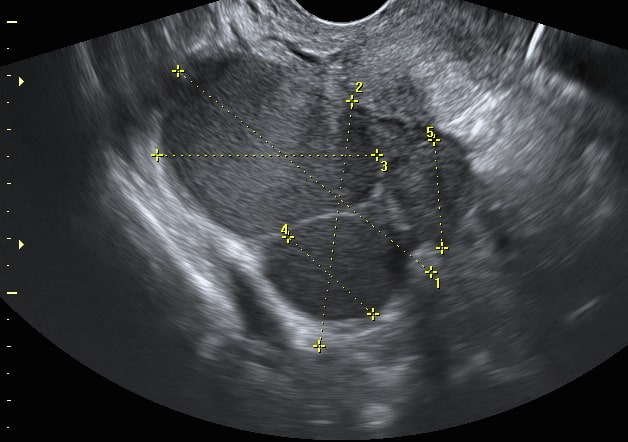

- Трансвагинальное УЗИ. Исследование может выявить изменения в структуре яичника, а также наличие кист и других новообразований с характерными признаками.